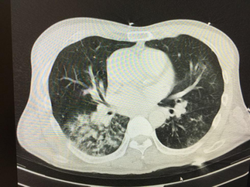

肺部感染ct图片怎么看,肺部感染ct图片

肺ct示肺部感染

这是病毒感染患者的肺炎ct片,是影像确诊是否感染的唯一依据和标准.

肺部感染ct图片

严重肺部感染ct图片

肺部感染的ct影像图片